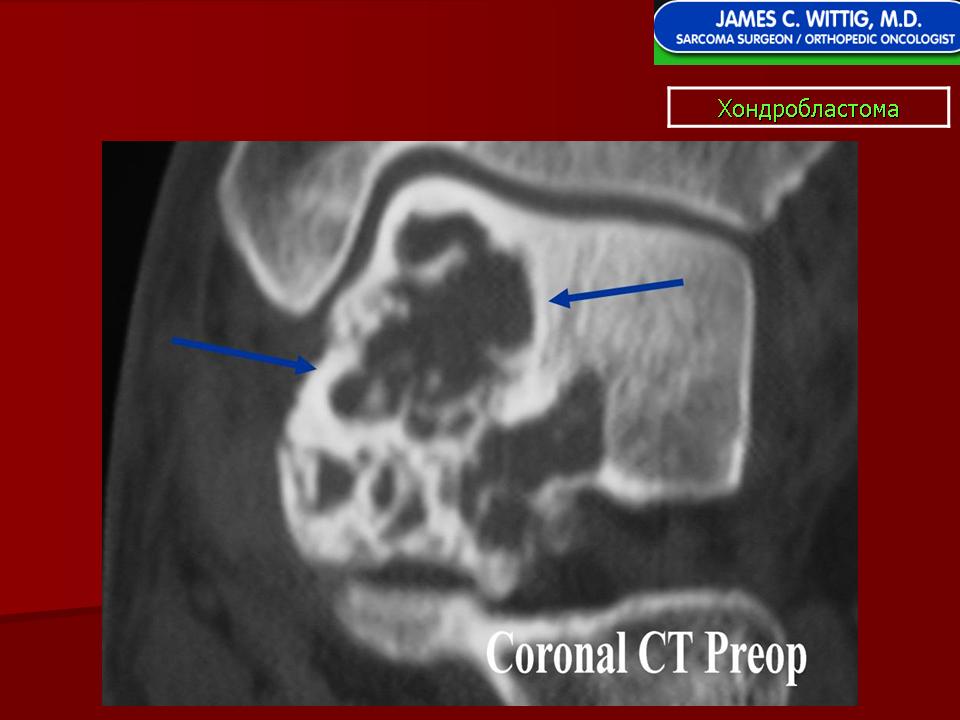

Рентгенологически хондробластома представляет собой сравнительно большой (2-4 см) очаг округлой формы, четко отграниченный от окружающей кости склеротической каймой. На фоне очага в большинстве случаев, но не обязательно определяются плотные включения, напоминающие хлопья ваты.

Рентгенологическая картина. Хондробластома выглядит как небольшой, от 3 до 6 см литический очаг, центрально или эксцентрично расположенный, с четкими контурами, занимающий около половины площади эпифизарной зоны. Хондробластома плоских костей и мелких трубчатых костей больших размеров, может сопровождаться припухлостью мягких тканей, вздутием кости и периостальной реакцией. Распространение процесса на метафизарную зону встречается часто.

Хондробластома — это редкая доброкачественная опухоль, локализующаяся, главным образом, в эпифизе и отличающаяся своеобразным клеточным составом. Ткань новообразования представлена овальными, округлыми и веретеновидными клетками, напоминающими незрелые хондроциты (хондробласты). Зрелый гиалиновый хрящ определяется лишь в некоторых опухолях. Возраст больных варьирует. Мужчины поражаются в два раза чаше женщин. Пациенты предъявляют жалобы на боли в течение нескольких месяцев или лет, у некоторых больных определяются внутрисуставной выпот, припухлость и ограничение движений. Наиболее типичная локализация опухоли — проксимальные эпифизы плечевой и большеберцовой костей, а также дистальный эпифиз бедренной кости. У 20 % больных опухоль развивается в плоских или коротких трубчатых костях, преимущественно в пяточной и таранной. Изредка поражаются кости лицевого черепа, в том числе височная. В большинстве случаев новообразование выходит за пределы эпифиза и распространяется на метафиз. На фоне остеолиза обнаруживаются рассеянные участки обызвествления в виде пунктирных линий, а также разреженный трабекулярный рисунок. Хондробластома, как правило, не выходит за пределы кости, но изредка проникает в полость сустава. В процессе роста опухоли иногда возникает вторичная аневризматическая костная киста.